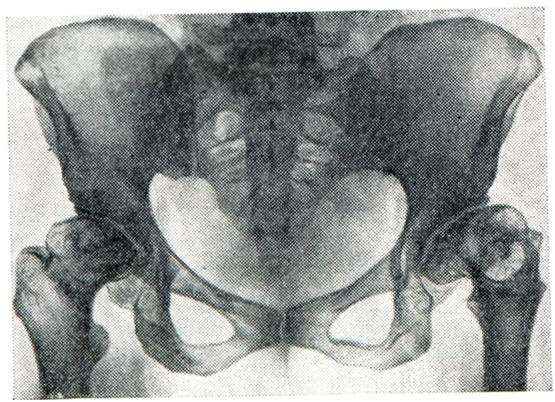

Вторичные артрозы характеризуются развитием изменений в суставных отделах костей на фоне первичного процесса, который рентгенологически может проявляться в виде деформации кости и изменения ее структуры. В результате основного процесса наиболее резко изменяется одна из костей, участвующих в образовании сустава. Остальные кости обычно (при отсутствии воспалительного процесса) страдают значительно меньше. Суставной конец кости деформируется, уплощается и нередко разрушается (рис. 8). Структура губчатого вещества кости подвергается перестройке, что проявляется остеолитическими и остеосклеротическими изменениями. В дальнейшем патологические состояния костей, образующих сустав, заканчиваются развитием вторичного артроза, степень выраженности которого зависит от характера основного процесса. При вторичном артрозе определяется сужение суставной щели, утолщение поверхностей костей за счет краевых костных разрастаний и образование очагов кистозной перестройки.

Информация об Ordo Deus Перейти в оглавление сайта

Рис. 8.

Вторичный артроз обоих тазобедренных суставов с деформацией головок бедренных костей и сужением суставных щелей (рентгенограмма).